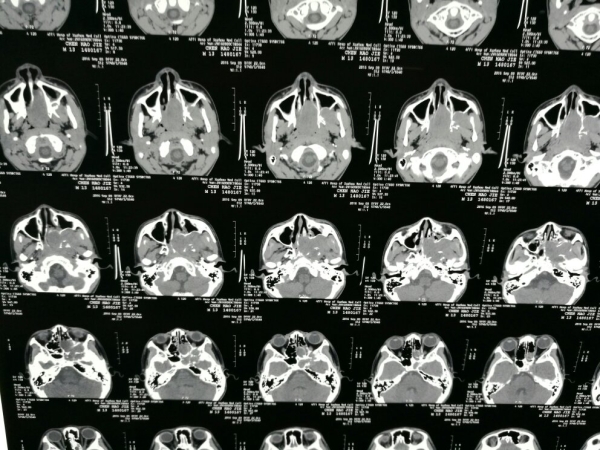

CT显示:左侧前中颅底部示不规则团块影,边界不清,密度欠均匀,临近骨质压迫、吸收,局部骨质欠连续,病变向筛窦、蝶窦、左侧鼻道、鼻咽腔、左侧眼眶及左侧颅内突出,与左侧海绵窦分界不清,左侧蝶窦、上颌窦及筛窦、左侧鼻甲形态不整,鼻咽腔变窄。

MR显示:左侧鼻咽腔、翼腭窝及筛窦富血供伴颅底骨破坏

初步诊断:鼻咽纤维血管瘤(Ⅳa期)。